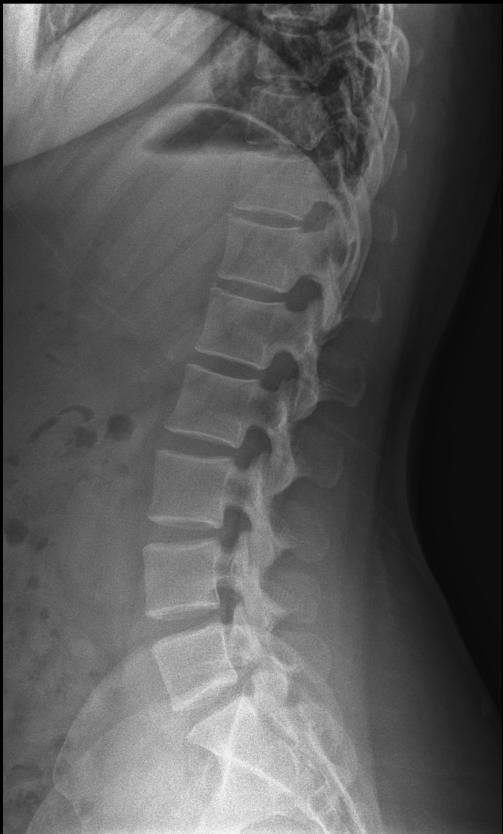

척추분리증인가요??(엑스레이 있어요)

한 병원에서는 척추분리증이라고 하고 한 병원에서는 척추분리증이 아니라고 해서요. 혹시 아래 사진에서 척추분리증 소견이 보이는 사진이 있나요??

여기까지가 a병원에서 찍은 사진이고 아래가 b병원에서 찍은 사진이에요!

A병원 세번째 사진의 아래 부위에 척추분리증이 있는게 맞습니다.

B병원 사진에서는 비교적 흐리게 보이지만 잘 보면 B병원 엑스레이에서도 같은 부위에 분리증을 확인할 수 있습니다.

두 사진을 비교해서 보았을 때 큰 문제가 있어 보이지는 않으며 엑스레이상 척추분리증 진단이 어렵거나 애매한 경우에는 추가적인 검사 MRI를 통해 진단을 받아보시는 것도 방법이라고 생각합니다.

제가볼때 엑스레이상에 분리증은 보이지않지만 각도에따라 그리고 기계에따라서 달라질수있으니 정확하게 하고싶다면 MRI검사를 추천합니다 감사합니다~

두가지 사진을 비교해보았을 때, 크게 특징적인 것이 관찰되지는 않습니다. 척추분리증을 진단하는 것은 임상증상과 영상검사를 통한 구조적 이상을 확인하는데요, 정확한 검진을 위해서는 ct나 mri같은 검사를 고려하시거나, 척추질환을 전문적으로 진단하는 병원급 의료기관에 방문해보시는 것도 고려해보시면 좋겠습니다.